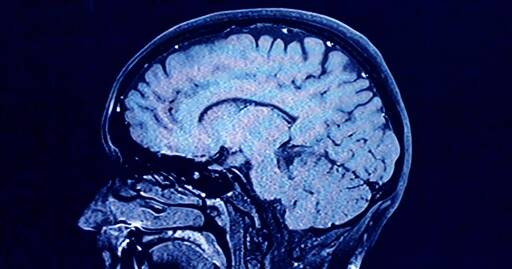

As we age, the human brain rewires itself. The process happens in distinct phases, or “epochs,” according to new research, as the structure of our neural networks changes and our brains reconfigure how we think and process information.

For the first time, scientists say they’ve identified four distinct turning points between those phases in an average brain: at ages 9, 32, 66 and 83. During each epoch between those years, our brains show markedly different characteristics in brain architecture, they say.

The findings, published Tuesday in the journal Nature Communications, suggest that human cognition does not simply increase with age until a peak, then decline. In fact, the phase from ages 9 to 32 is the only time in life when our neural networks are becoming increasingly efficient, according to the research.

During the adulthood phase, from 32 to 66, the average person’s brain architecture essentially stabilizes without major changes, at a time when researchers think people are generally plateauing in intelligence and personality.

Then, from 66 to age of 83, the brain tends toward “modularity,” where the neural network is divided into highly connected subnetworks with less central integration. At age 83, connectivity declines further.